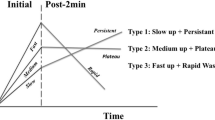

Kuhl CK, Mielcareck P, Klaschik S, Leutner C, Wardelmann E, Gieseke J, et al. Dynamic breast MR imaging: are signal intensity time course data useful for differential diagnosis of enhancing lesions? Radiology. 1999;211(1):101–10.

Petrillo A, Fusco R, Petrillo M, Granata V, Bianco F, Di Marzo M, et al. DCE-MRI time-intensity curve visual inspection to assess pathological response after neoadjuvant therapy in locally advanced rectal cancer. Jpn J Radiol. 2018;36(10):611–21.

Fabijanska A. A novel approach for quantification of time-intensity curves in a DCE-MRI image series with an application to prostate cancer. Comput Biol Med. 2016;73:119–30.